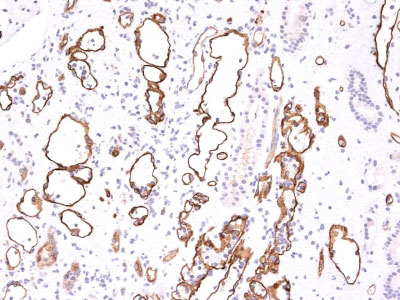

Formalin-fixed, paraffin-embedded human Kidney Transplant stained with Complement 4d Monoclonal Antibody (C4D204).

Formalin-fixed, paraffin-embedded human Kidney Transplant stained with Complement 4d Monoclonal Antibody (C4D204). |